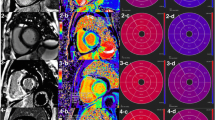

Beside development of heart failure symptoms, amyloidosis may initially lead to apparent left ventricular (LV) wall thickening mimicking left ventricular hypertrophy (LVH). Cardiovascular magnetic resonance (CMR) imaging is recommended as the diagnostic tool of choice in LVH as it can help differentiate cardiac amyloidosis from other potential causes of a cardiomyopathy (Fig. 1a) [15,16,17]. The presence of global diffuse myocardial late gadolinium enhancement (LGE) pronounced in the subendocardial layers is common in cardiac amyloidosis (Fig. 1b), and has been associated with poor prognosis [18]. Besides LGE, only few other markers, such as global longitudinal strain (GLS), are available for risk stratification in AL patients [19].

Representative cardiovascular magnetic resonance (CMR) images of a) a patient with light chain (AL) amyloidosis demonstrating global left ventricular (LV) wall hypertrophy, pericardial effusion and both-sided pleural effusions, b Late gadolinium enhancement (LGE) pronounced in the subendocardial layers in cardiac amyloidosis (marked with a red line) and c) long axis strain (LAS) measurement

CMR measurements of LV end-systolic volume, LVEF, mass as well as strain analysis demonstrated a significant difference in patients who met the composite endpoint (Table 1). Standard two-dimensional (2D) GLS was reduced in all AL patients (− 13.7 ± 5.5%) with a significant difference in both groups of the secondary composite endpoint (− 15.4 ± 5.9% vs. -12.2 ± 4.7%, p = 0.011). In addition, the segmental longitudinal strain analysis demonstrated normal longitudinal strain of the apical segments, while basal segment strain segments were significantly reduced (longitudinal strain values of basal segments: − 12.8 ± 10.7, midwall segments: − 17.2 ± 11.7 and apical segments: − 22.4 ± 11.1, p < 0.01). However, the segmental analysis did not significantly differ between both groups (Table 1).